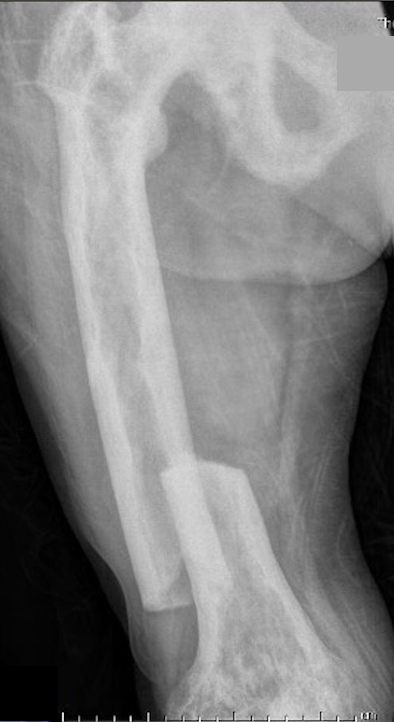

Femur

Tibia

Tibia deformity - sabre tibia

Fracture

Issues

Paget's fractures likely have normal healing capacity

Hard bone - difficult entry points

Bleeding

Deformity - may require osteotomy prior to IM nails